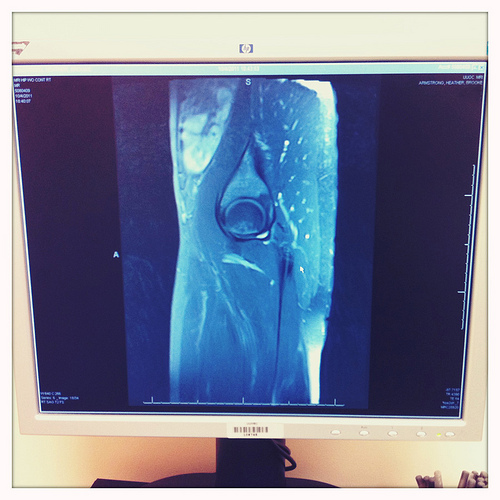

After two sets of x-rays, one for my back and one for my hip, the doctor and his assistant confirmed that it wasn’t a disc issue (THANK GOD), but they couldn’t rule out a stress fracture. So I’d need to schedule an MRI. Ooh, fun! This NYC marathon is crossing off so many things on my bucket list! See: being trapped inside a giant, deafening machine emitting a nuclear magnetic field.

I wouldn’t see my doctor until this morning, so I had an entire night to imagine all sorts of horrible things, the worst one being that I’d have to drop out of the marathon. I know, it’s not cancer or starvation or unemployment. There are far more horrible things in life. But the idea of having to sit out that race, especially with all the mileage I’ve put in already (73 miles in four weeks), especially since it’s with such a fantastic team for such a worthy cause… I felt like someone had punched me in the gut.

This morning I hobbled into the orthopedic clinic prepared for the worst. And when the doctor pulled up my MRI I totally expected to see a skull and crossbones etched into my hip. No, a laughing skull and crossbones. THE GLASS IS HALF EMPTY.

But there was no fracture. There was no break. Everything looked perfectly normal except for the inflamed muscle there around my right hip. Was there anything they could do for it? He was so glad I asked! Yes! I’d just need to drop my pants and stick my butt in his face so that he could inject it with a shot of cortisone!